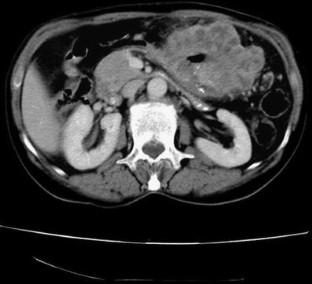

We report a Spanish female who consulted because of fatigue, anorexia, and weight loss. In laboratory data, she presented anemia and markedly elevation of AFP. On CT scan, a gastric mass resulted without hepatic dissemination, and subsequently, gastroduodenoscopy was performed for histological diagnosis. Then, an ulcerated mass was detected and sample was taken, resulting in poorly-differentiated adenocarcinoma of stomach with hepatoid tissue foci, with intense positivity for AFP-immunohistochemical staining. This rare cancer has poor prognosis even with early gastrectomy and chemotherapy.

Fig. 3